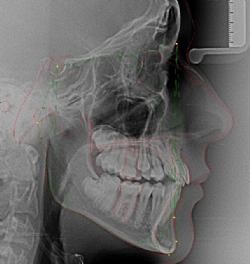

Seitliche Fernröntgenaufnahme

Durch eine seitliche Aufnahme des Schädels erhält man Informationen über den Aufbau des Gesichtes, Beziehung der Kiefer zueinander sowie zur Schädelbasis, über die Wachstumsrichtung der Kiefer und die Neigung der Frontzähne. Durch spezielle Vermessung der anatomischen Strukturen ergeben sich wichtige Hinweise für die Therapieplanung und den Behandlungsablauf.